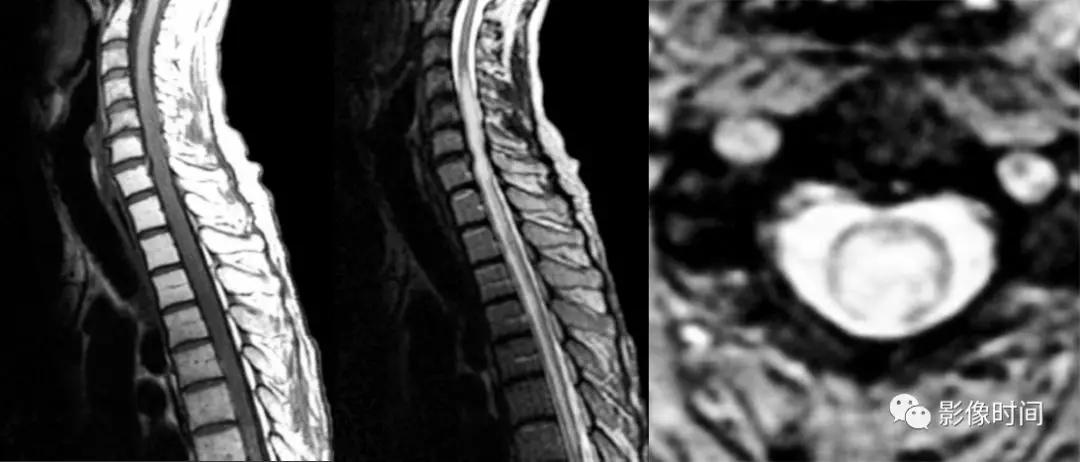

神经脊髓炎谱系疾病(neuromyelitis optica spectrum disorder,NMOSD):是一种由水通道蛋白-4(AQP-4)自身抗体介导的炎性脱髓鞘疾病,青年或中年女性较多见,临床常为双侧视神经炎和脊髓炎导致失明和截瘫,也可累及大脑。

MRI:

脊髓:病灶 T2WI 呈高信号,T1WI 呈稍低信号,急性期出现斑片状或云雾状强化,轴位常位于脊髓中央,长度>3 个椎体长度。亮点征:轴位 T2WI 很高信号的多发斑点,信号高于脑脊液,特异性=97%。

病灶分布于脊髓中央,长度大于3个椎体,亮点征

多发性硬化(Multiple sclerosis,MS)亦是一种严重的中枢神经系统自身免疫脱髓鞘病变,免疫球蛋白分泌 B 细胞和浆细胞的克隆性扩增,可使 CSF 中出现寡克隆带特征。

脊髓:颈髓较常受累,病灶 T2WI 呈高信号,T1WI 呈稍低信号,轴位常分布于前索、侧索或者后索,长轴 ≤ 2 个连续阶段椎体,急性期呈斑片状、结节状或环形强化。

病灶位于侧索、长度小于3个椎体节段